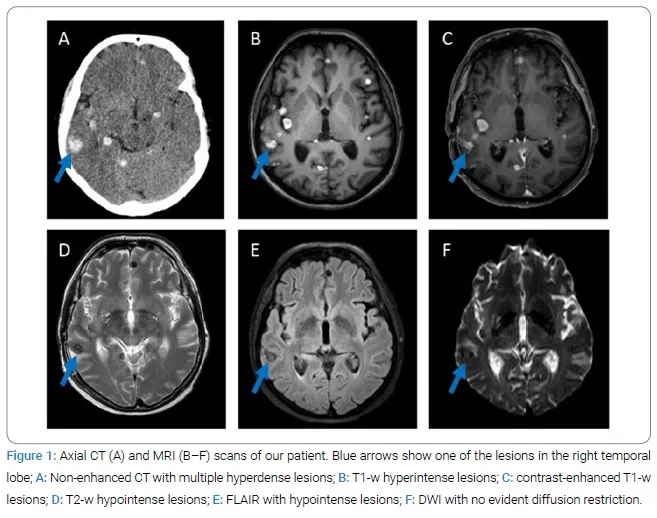

- Brain Abscess: MRI: Central DWI restriction, ring enhancement. MRS: ↑Lactate, amino acids.

- Neurocysticercosis (NCC): MRI: Stages (Vesicular + scolex, Colloidal, Granular, Calcified). 📌 VesCo GraCa.